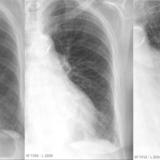

APE 2

Date: 11/05/2005

Views: 2808